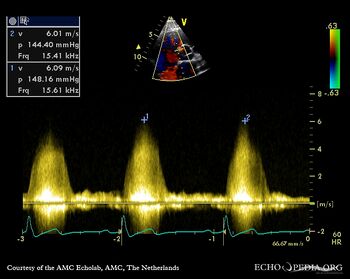

PSAX with Color Doppler Continuous-wave Doppler signal of flow through ventricular septum defect